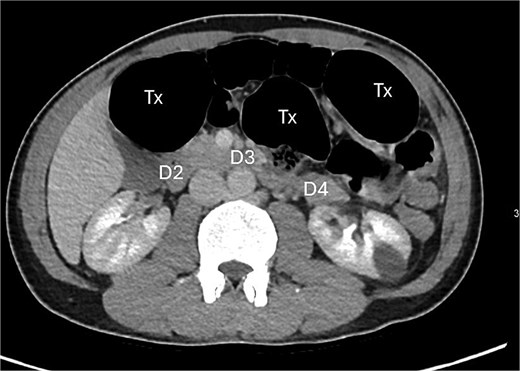

A contrast-enhanced computed tomography (CT) scan of the abdomen and pelvis demonstrated a large bowel obstruction with a transition point at the distal transverse colon with swirling of the mesentery. Downstream large bowel was collapsed. Upstream dilatation included the terminal ileum suggested an incompetent ileo-caecal valve. The gastric antrum was also involved in the internal hernia, resulting in gastric outlet obstruction. See Figs 1–5.

Axial CT image displaying transverse colon in paraduodenal hernia (PDH) with resulting distension of transverse colon (Tx) and stomach (st).

Posterior displacement of the duodenum (D4) due to herniated transverse colon.